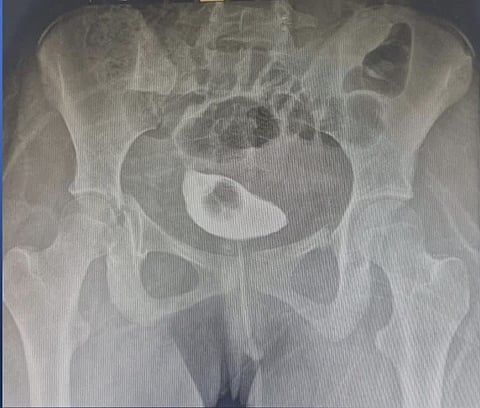

نجح مستشفى الملك سلمان، عضو تجمع الرياض الصحي الأول، من إعادة الحركة لمريضة تبلغ من العمر 15 عامًا؛ عبر إجراء جراحي تم بواسطة رد مفتوح لكسر الحوض وتثبيته بواسطة شريحة ومسامير طبية، قام بها الفريق الطبي بقيادة د. سلطان باطيب.

يذكر أن المستشفى استقبل الحالة من منطقة القصيم، وهي تعاني من كسور في الحوض؛ إثر تعرضها لحادث مروري.